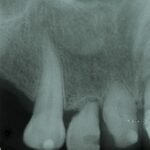

Punto Bajío Casos Clínicos Prótesis Fija sobre Implante unitario Inicio Provisional Final Prótesis Parcial Fija sobre 2 Implantes 2 Implantes Final Prótesis Bucal Removible Inicial Inicial Superior Inicial Inferior Rayos X Inicial Rayos X Inicial Frontal Final Final Superior Final Inferior Prótesis Parcial Fija/ Coronas de Circonio Sonrisa Inicial Foto Inicial Foto Inicial Inferior Foto Final Inferior Foto Final Sonrisa Final Prótesis Total Protesis Inmediatas 1 Protesis Inmediatas 2 Prótesis Removible/ Coronas Metal-Ceramica Carillas Incrustaciones Endodoncia